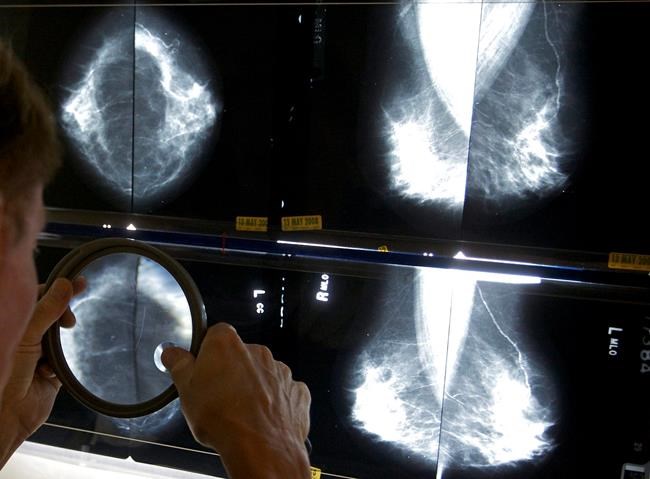

Researchers say a decades-old Canadian study that influenced breast cancer screening policy contained significant flaws in its approach, leading to a “substantial impact” on disease outcomes and potentially contributing to hundreds of “avoidable deaths” per year.

Two trials — collectively known as the Canadian National Breast Screening Study (CNBSS) — found that mammograms for women in their 40s did not reduce death rates from breast cancer.

They say more recent findings suggest there are benefits to mammography screening for women under 50, including a 2014 observational study that indicated that giving people mammograms in their 40s was associated with a 44 per cent reduction in breast cancer deaths.

The Canadian Task Force on Preventive Health Care doesn’t currently recommend mammograms for people aged 40 to 49, unless a pre-existing factor puts them at a higher-than-average risk — for example, if a family member had breast cancer or if they have the BRCA gene.